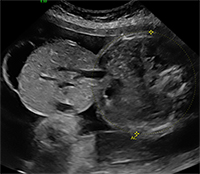

Omphalocele (pronounced OHM-fal-o-seal) is a birth defect that affects the abdominal wall. When the abdominal wall doesn’t form correctly, the bowel and other abdominal organs can be partially within the umbilical cord and covered by a thin membrane.

In a normally developing fetus, as the bowel grows, it will move into the umbilical cord until about 10 weeks, and return to the abdomen by 11 weeks. If the bowel does not move back into the abdomen and stays within the umbilical cord, an omphalocele occurs.

Omphaloceles can range in size from a small hernia with a relatively straightforward repair, to a large defect (commonly called a “giant” omphalocele) that must be repaired in stages.

Over the past five years, UR Medicine's Maternal-Fetal Medicine has cared for and evaluated more than 50 fetuses with omphalocele diagnosed in utero. Our OB/GYN ultrasound unit is certified by the American Institute of Ultrasound in Medicine to perform Level II ultrasounds, a more in-depth evaluation.

Our experienced Registered Diagnostic Medical Sonographers and state-of-the-art equipment including 3D/4D capabilities help diagnose omphalocele effectively.